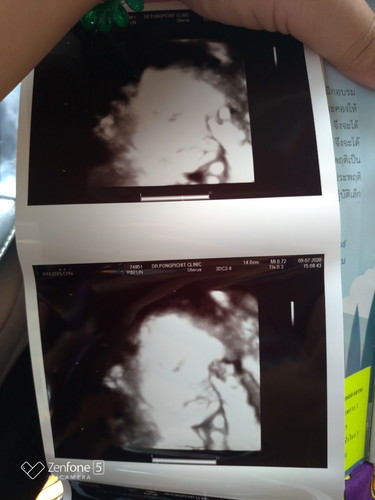

ช่วยดูรูปตรงปากน้องหน่อยค่ะว่าปกติไหม

ไม่แน่ใจว่าน้องทำเหมือนปากจู๋ หรือจะอ้าปาก หรือยังไงคะ แม่กังวลมาเป็นอาทิตย์กับรูปที่เห็นค่ะ กลัวน้องเป็นปากแหว่งไรงี้ รึแม่คิดไปเอง ช่วยบอกให้แม่ชื่นใจทีว่าปกติหรือไม่คะ

ถ้าปากแหว่ง คุณหมอน่าจะแจ้งแล้วนะคะ